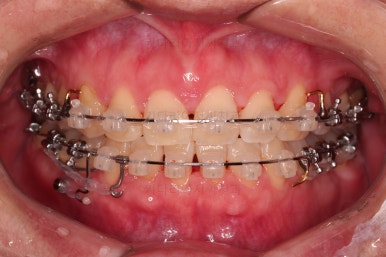

브라켓을 부착합니다.

이번 환자분이 선택하신 장치는 데이몬 클리어라고 하는 자가결찰 세라믹 장치인데요.

일반적으로 흔히 아시는 클리피씨 장치에 비해서 철사를 잡아주는 뚜껑까지 세라믹으로 되어 있어서 아마도 현존하는 세라믹 장치 중에서는 가장 심미적인 장치라고 볼 수 있습니다.

대신, 세라믹으로 되어 있다보니 강도 때문에 부피는 조금 더 커진다는 단점은 있긴 합니다.

장치 부착 직후의 웃는 모습과 입이 좀 더 나오는 양상을 참고해 주시고요.

발치 공간을 적극적으로 줄여 나갑니다.

이 과정에서 입매, 앞니 각도, 정중선 등을 신경 써줍니다.

중앙선 개선을 위해 미니스크류와 다양한 장치를 활용해 주고요.

중앙선, 교합 등을 더 신경쓰고 마무리를 합니다.